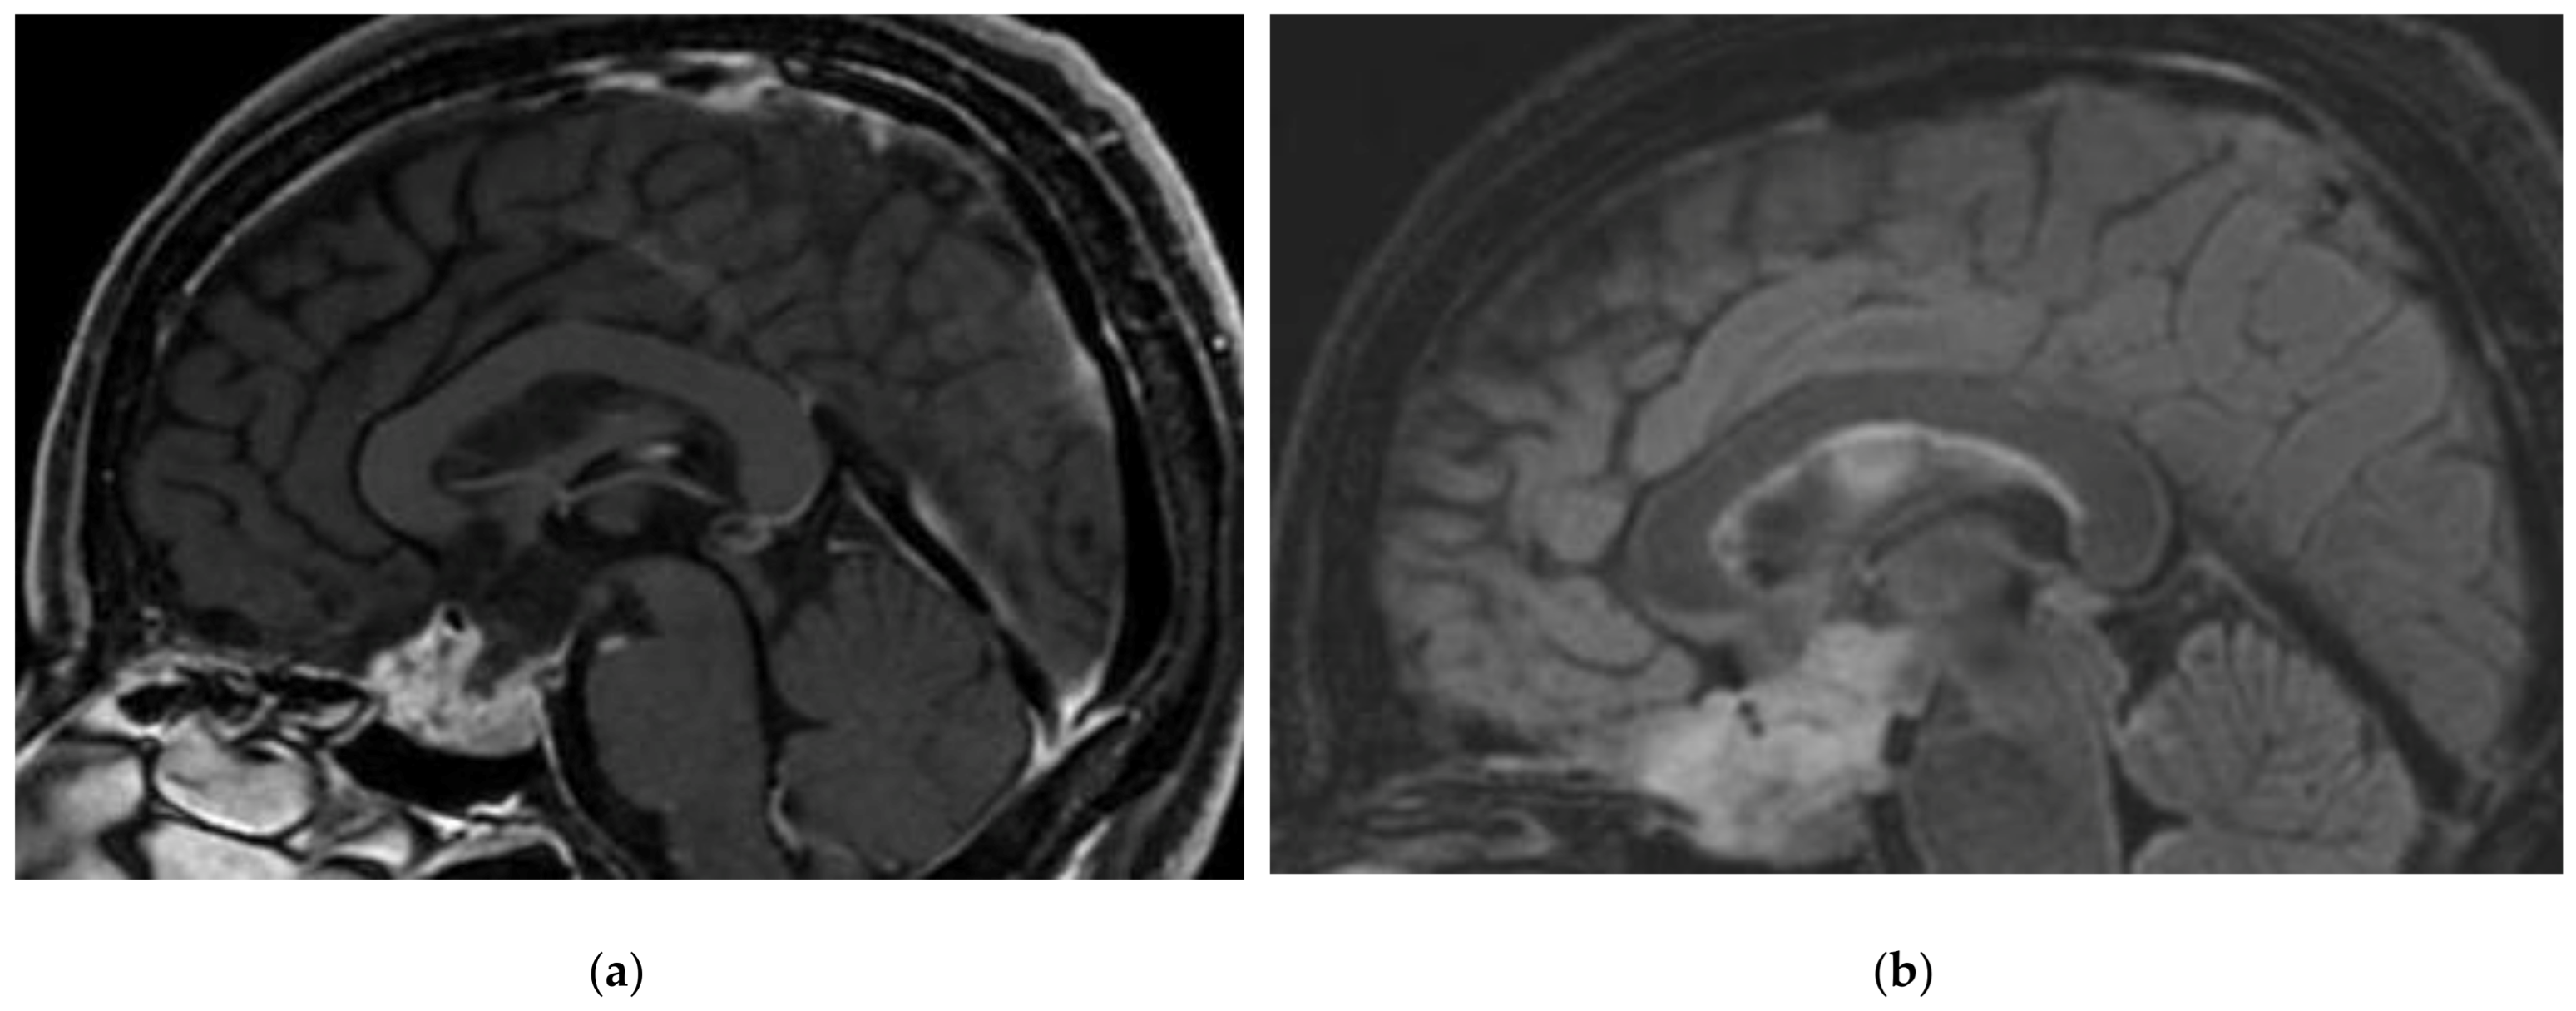

2.1. Dysplastic Cerebellar Gangliocytoma (Lhermitte–Duclos Disease, DCG)

- Dhamija, R.; Wood, C.P.; Porter, A.B.; Hu, L.S.; Weindling, S.M.; Hoxworth, J.M. Updated Imaging Features of Dysplastic Cerebellar Gangliocytoma. J. Comput. Assist. Tomogr. 2019, 43, 277–281. [Google Scholar] [CrossRef] [PubMed]

- Joo, G.J.; Doumanian, J. Radiographic Findings of Dysplastic Cerebellar Gangliocytoma (Lhermitte-Duclos Disease) in a Woman with Cowden Syndrome: A Case Study and Literature Review. J. Radiol. Case Rep. 2020, 14, 1–6. [Google Scholar] [CrossRef] [PubMed]